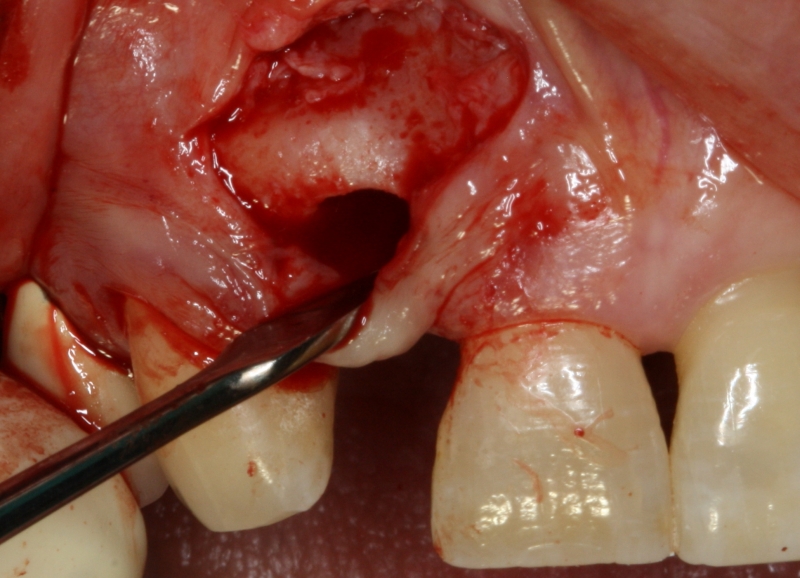

16/20 - re-entry: maxresorb® particles integrated into newly formed boneGBR with maxresorb® & Jason® membrane - Prof. Dr. Dr. D. Rothamel